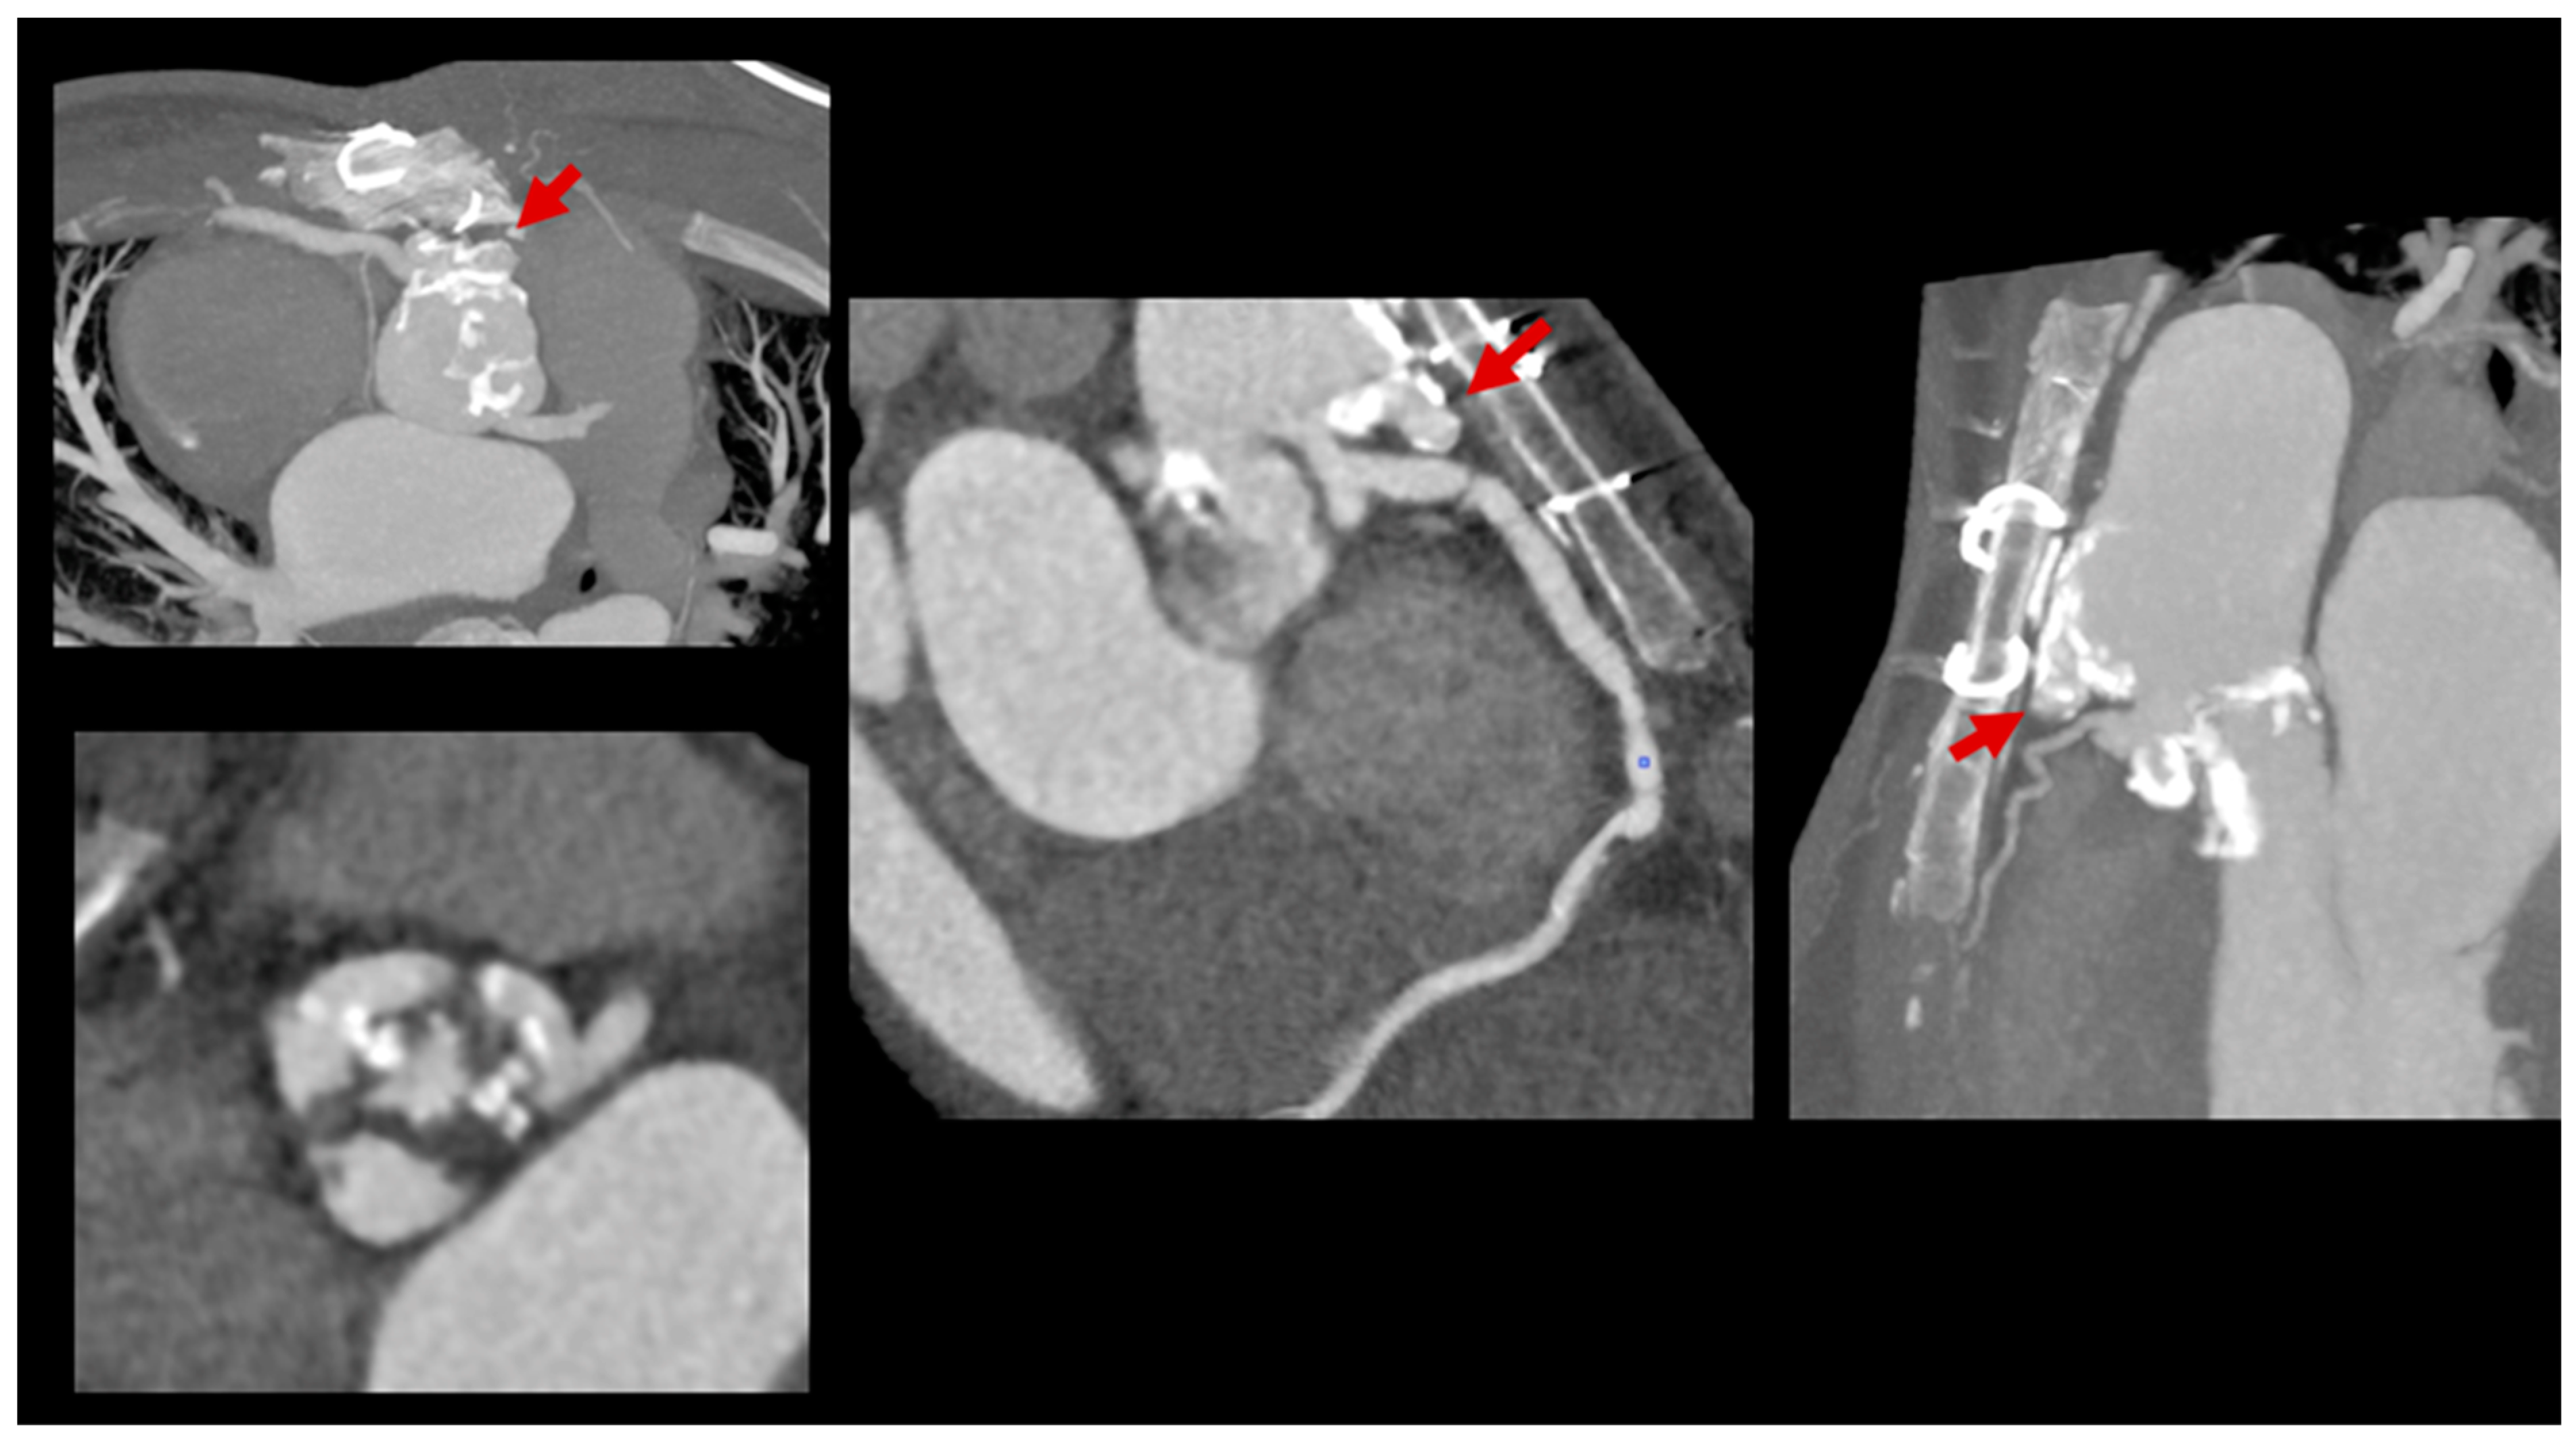

3.3. Role of Cardiac Computed Tomography

- Thaler, C.; Witt, D.; Casey, S.; Kelle, A.M.; Garcia, S.; Lesser, J.; Han, B.K. Diagnostic Value of Computed Tomography Angiography for Infective Endocarditis After Right Ventricle Outflow Tract Repair. J. Am. Coll. Cardiol. Case Rep. 2023, 23, 102011. [Google Scholar] [CrossRef] [PubMed]